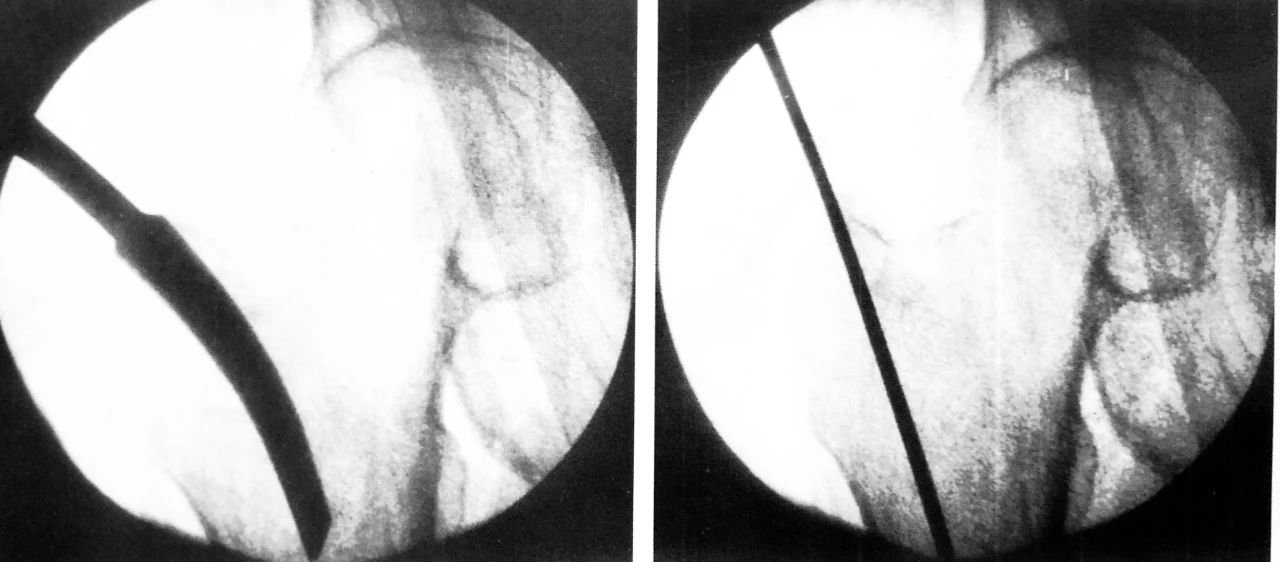

C 形臂下操作步骤,尖端开髓、插入导针

扩髓、主钉置入

正位拉力钉导针位置、侧位拉力钉导针位置

阶梯钻钻孔、正位拉力钉位置

侧位拉力钉位置、远端锁钉置入